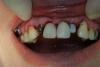

bullbull Опубликовано 20 марта, 2013 Поделиться Опубликовано 20 марта, 2013 Работа более чем двухгодичной давности. Запротезирована пациентка уже давно. Проблема в том, что уехала в Питер на ПМЖ - наблюдать нет возможности.Интересно ваше мнение о работе. 1 Ссылка на комментарий

bullbull Опубликовано 20 марта, 2013 Автор Поделиться Опубликовано 20 марта, 2013 Зубы леченые-перелеченые, под пломбировочным материалом кариес. Приняли решение, что ортодонтически не вывезем.На 4-м фото аутомембрана из ОбТП. Всегда использую при имплантации, кладу перед ушиванием. Ссылка на комментарий

DShu Опубликовано 20 марта, 2013 Поделиться Опубликовано 20 марта, 2013 Не маловато места для 3,75?Сосочков не будет походу. Особенно между 21 и 22.И платформу надо было небнее ставить на мой взгляд.Есть отдаленные фото? 1 Ссылка на комментарий

Alexey Doc Опубликовано 22 марта, 2013 Поделиться Опубликовано 22 марта, 2013 (изменено) Работа более чем двухгодичной давности. Запротезирована пациентка уже давно. Проблема в том, что уехала в Питер на ПМЖ - наблюдать нет возможности.Интересно ваше мнение о работе.Какая толщина костной ткани между поверхностью имплантата и корнями зубов справа и слева?? по фото создалось впечатление что её (костной ткани) там практически нет! Изменено 22 марта, 2013 пользователем Alexey Doc Ссылка на комментарий